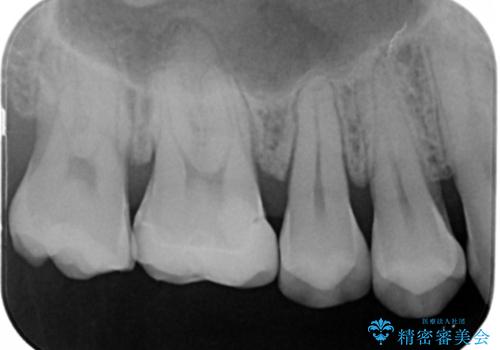

- 右上6番の銀歯をセラミックに変えたいと希望された患者様です。

切削量、形態を考慮し、セラミックインレーでの治療を計画しました。

銀歯と虫歯を除去した上でCRで裏層し形態を整えて印象を行っています。